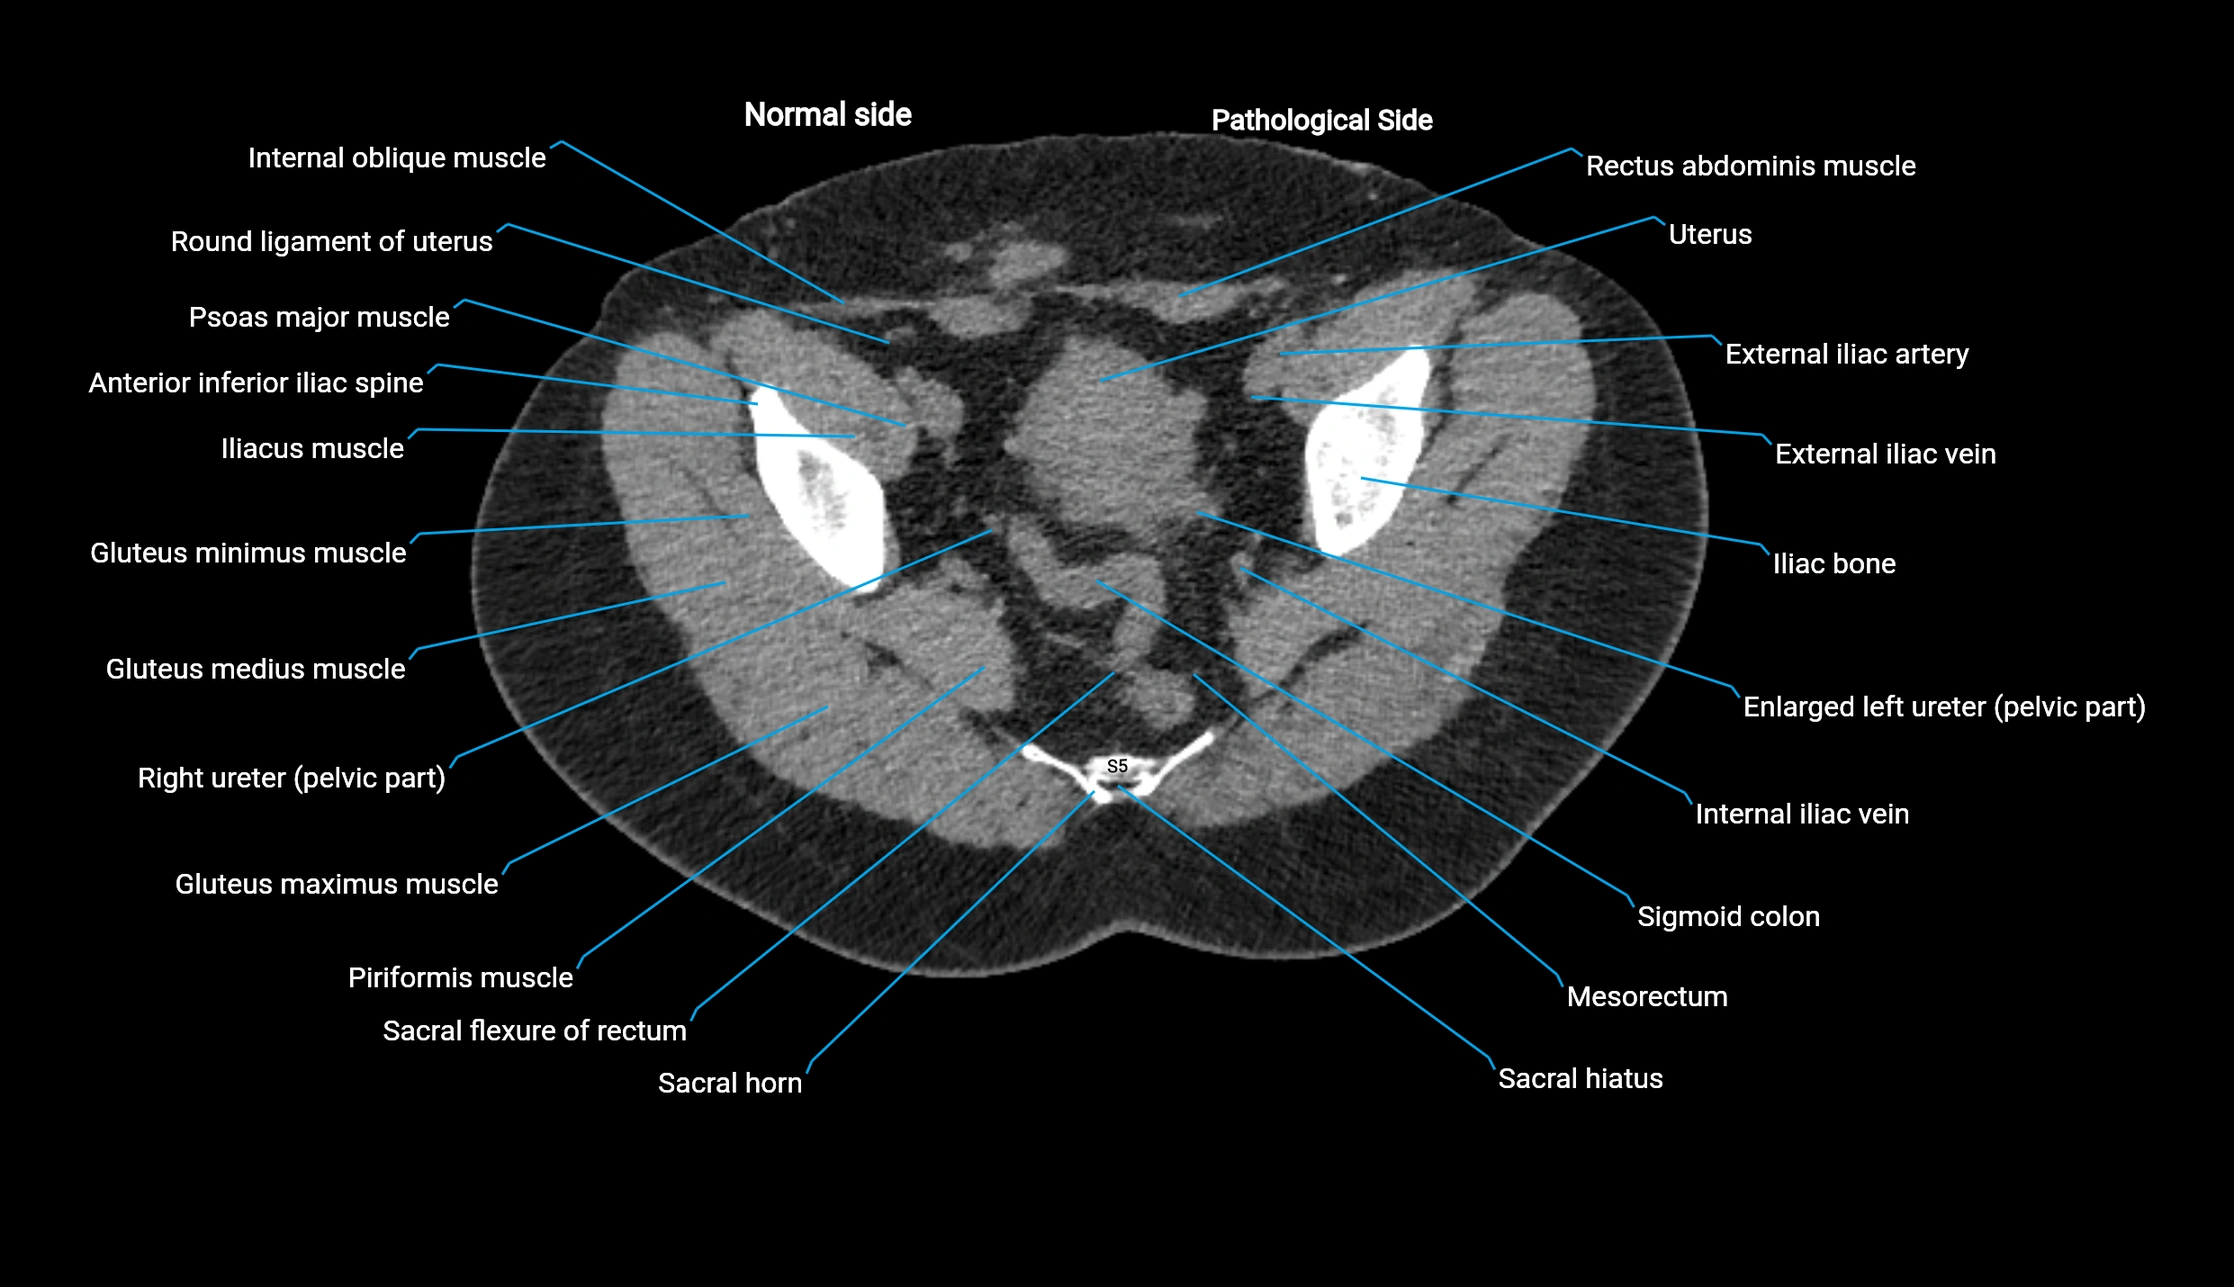

CT image

image